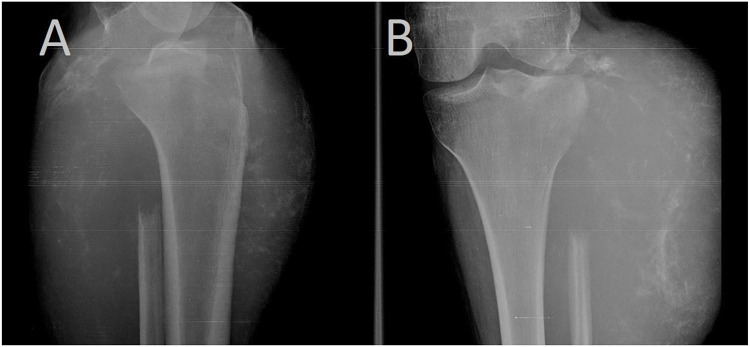

Case presentation: A 21-year-old female patient was admitted to the hospital with a mass on the upper lateral aspect of the left leg. She reported the onset of a small swelling in the left leg eight months prior to admission. It has gradually increased in size to involve the upper leg and part of the knee. The patient had limited range of motion in the knee joint and difficulty leaning on the affected limb. Radiographs showed a cortical-destroying osteolytic lesion at the head of the fibula extending into the surrounding soft tissue. Ultrasound imaging showed a mixed echo formation with indistinct borders and multiple chambers separated by trabeculae demonstrating blood flow. MRI revealed the absence of the fibular head as evidenced by cortical destruction and extension into adjacent soft tissue. CT scan showed a 12×13 cm mass in the left popliteal region extending to the knee margin. Enlarged lymph nodes were noted in the left groin. Multiple small metastases were observed in the lungs. Histologically, atypical epithelial cells and stromal spindle cells were observed. CK and CK19 staining was positive. The patient was treated with Sunitinib 50 mg orally, once daily for 4 weeks, followed by 2 weeks off for 2 cycles. During treatment (after 2 cycles) the tumor showed progressive growth, resulting in decreased function of the affected limb. She was referred to the surgical department where the appropriate surgical amputation was performed. After surgery, the patient's general condition improved. A further CT scan revealed a slight progression of metastatic lesions in the lungs, which prompted the decision to administer chemotherapy, but she refused to continue the treatment and did not receive chemotherapy. Two months later, she presented to the hospital in poor general condition. CT scan revealed extensive and progressive lesions in both lungs, leading to chest pain, hemoptysis, and hypoxia. Despite supportive care, the patient eventually died.